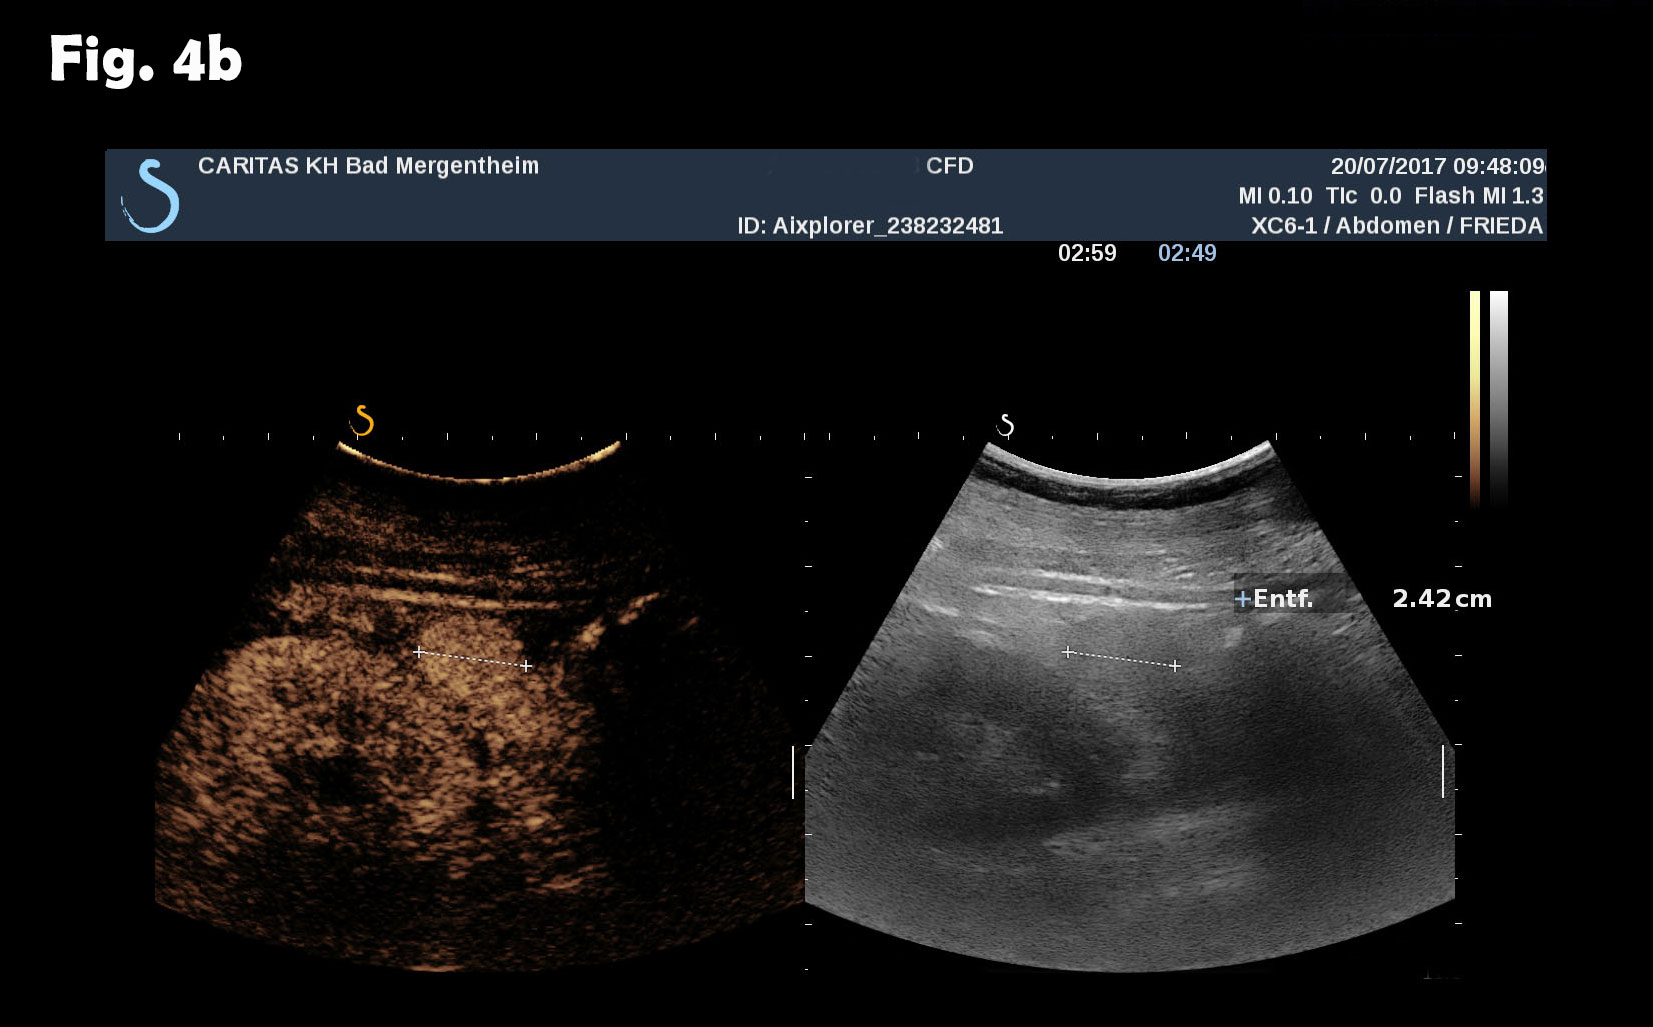

Computed tomography of the chest revealed pneumonic infiltration but was otherwise normal. The endoscopic examination of the upper and lower gastrointestinal tract was normal. Contrast enhanced ultrasound (CEUS) showed arterial and late phase enhancement lasting more than 5 minutes in all examined nodules. After Biopsy the ultrasound examination was performed showing multiple almost echofree but also echogenic round and oval shaped focal peritoneal masses with a size of up to 46 mm [Figure 2-4].

Figure 3: The same lesion as shown in Figure 2. Contrast enhanced ultrasound revealed arterial (a) and late phase enhancement lasting > 4 minutes (b).

Figure 4: At different abdominal locations more echogenic round oval lesions upt to 30 mm were identified by ultrasound. The lesions were best depicted during the late phase enhancement behind the accessory spleen next to the lesion shown in figure 2 (a) and elsewhere in the abdomen (b). The Figure 3c represents the CT finding shown in figure 1.